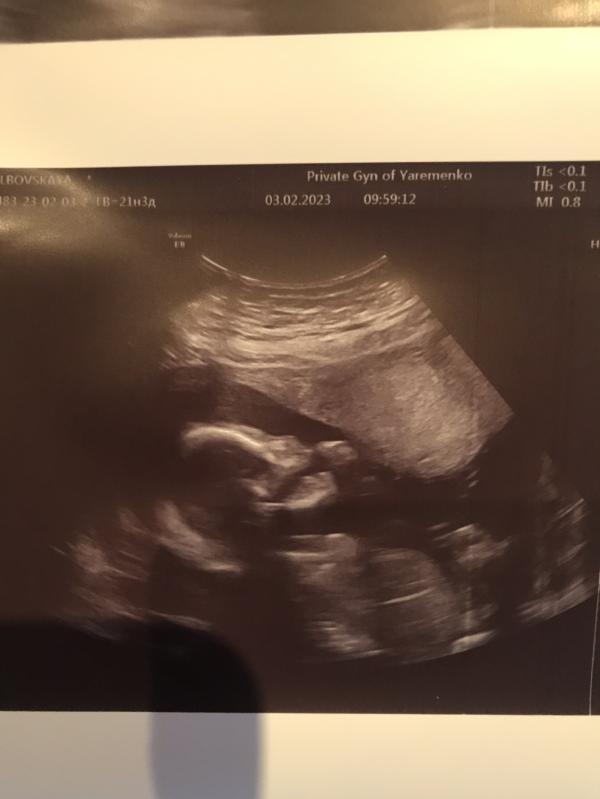

Всем привет:) были сегодня на 2 скрининге, у Ярьоменко. Осталась довольна врачом, хотели видео 3д на память, но ребёнок не удобно лежал:) в другой раз сказал сделаем, на узи сердца нужно идти к нему в 20-х числах марта. По скринингу все ок, отклонений никаких нет:))) Подтвердил пол, будет малышка, доченька, муж очень рад, сидел со мной и тоже смотрел:) Врач сделал фото как малая руку в рот засовывала, открывала рот:)

Яременко - врач супер! Все скрининги делала у него, и пол нам определил уже на 13 недели.

Нет, я первый делала по месту где стала на учёт, в 5 роддоме возле ЮЖД. Второй уже у него, врач хороший, внятный, сдержанный, ничего лишнего не сказал, все по факту,врач высшей категории, я даже так скажу, моя мама была у него со мной, он меня на узи видел, подтвердил маме что у неё будет девочка) Очень советую Ярьоменко) первый раз мне пол сказали на 15 неделе, я не сдержалась и пошла узнавать к Ткачеву в Доктор Алекс)